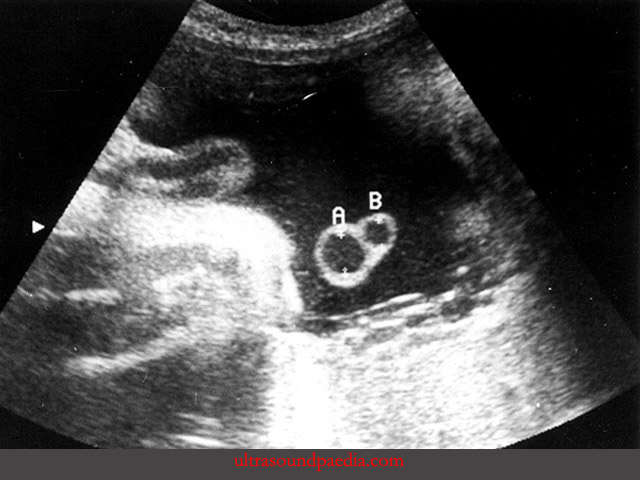

Dây rốn bình thường có ba mạch máu, gồm hai động mạch và một tĩnh mạch. Khi thai chỉ có một động mạch rốn, tình trạng này được gọi là dây rốn một động mạch. Trên mặt cắt siêu âm, lúc này chỉ còn thấy hai mạch nên nhiều nơi gọi là dây rốn hai mạch. Trong hồ sơ siêu âm, tình trạng này thường được ghi tắt là SUA viết tắt của Single Umbilical Artery.

Có một bẫy hay gặp khi đánh giá số mạch dây rốn. Nếu chỉ quan sát đoạn dây rốn gần bánh nhau, hai động mạch có thể dính vào nhau trong một đoạn ngắn. Khi đó, hình ảnh dễ bị hiểu nhầm thành dây rốn hai mạch. Để tránh nhầm lẫn, cần kiểm tra mạch máu chạy hai bên bàng quang của thai. Nếu chỉ thấy mạch ở một bên, điều này ủng hộ chẩn đoán chỉ còn một động mạch rốn.